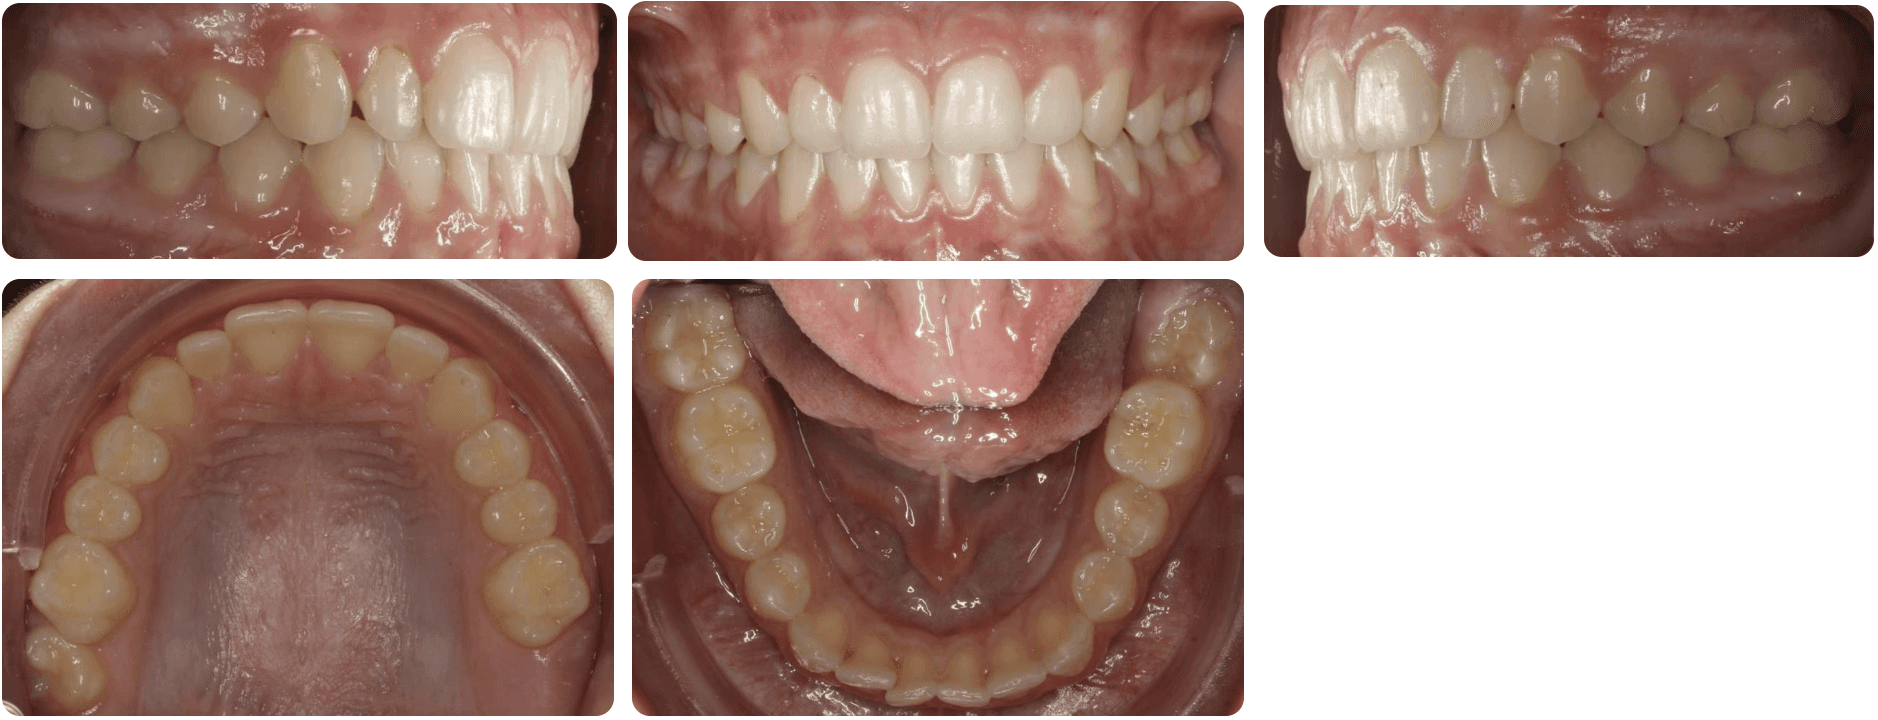

Initial treatment

INTRAORAL